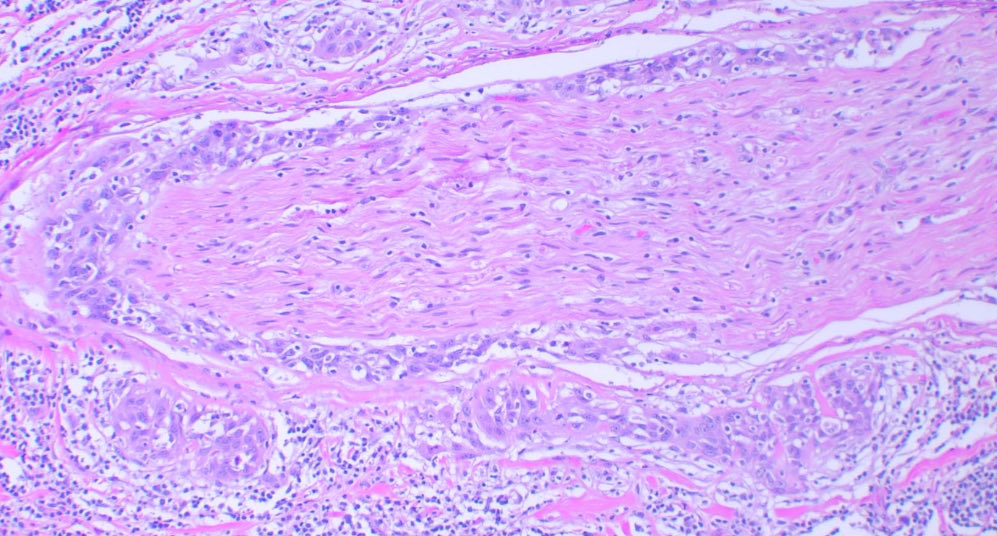

Cutaneous Squamous cell carcinoma Perineural invasion 😢 #path #dermpath #pathology #cancer